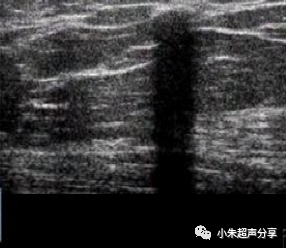

病例2 女 ,5岁,项部毛母质瘤,

其内未见血流信号